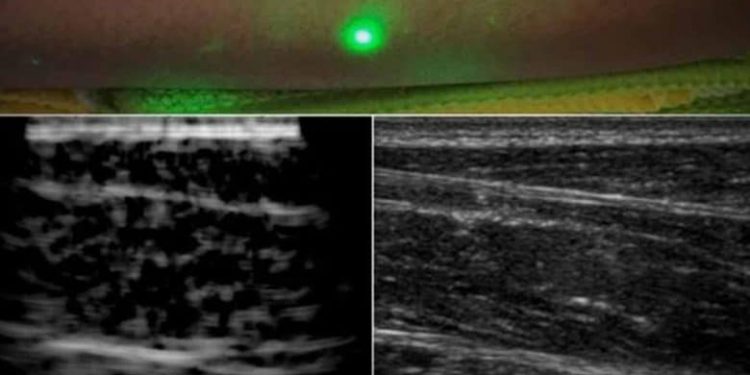

New York: Engineers at Massachusetts Institute of Technology have come up with an alternative to conventional ultrasound that does not require contact with the body to see inside a patient.

The new laser ultrasound technique leverages an eye- and skin-safe laser system to remotely image the inside of a person, which may one day allow doctors to assess the health of infants, burn victims, and accident survivors in hard-to-reach places from the comfort of their chambers.

In a paper published by Nature in the journal Light: Science and Applications, the team reported generating the first laser ultrasound images in humans.

The researchers scanned the forearms of several volunteers and observed common tissue features such as muscle, fat, and bone, down to about 6 centimetres below the skin.

These images, comparable to conventional ultrasound, were produced using remote lasers focused on a volunteer from half a metre away.

In this unconventional ultrasound method, when trained on a patient’s skin, one laser remotely generates sound waves that bounce through the body, said the study.

A second laser remotely detects the reflected waves, which researchers then translate into an image similar to conventional ultrasound, it added.